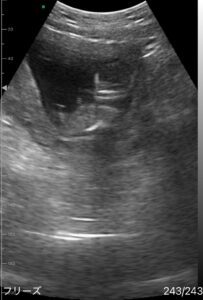

投稿に映っていたエコーは、妊娠4ヶ月、13週のときのものです。

この映像は、医療機関での健診時ではなく自宅用のレンタル機器を使って撮影したものでした。

ママさんは、家で毎日エコーを見ることを日課にしています。

その日は、いつもより長めにエコーを見ていたといいます。